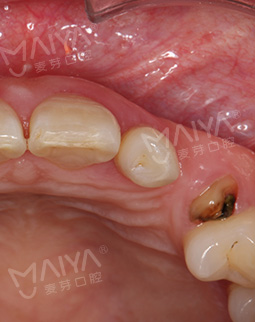

从此,不太美观的牙齿直接影响了我的的生活与社交!尤其在青春期那个时候,别人突然看我的牙齿空隙,我就有点尴尬甚至有点自卑,所以我尽量不露牙齿笑,这一点还是很影响交友的....然而一味的放任不管,牙齿终究还是出了问题,邻牙失去支撑,在日常饮食和咀嚼中受到了影响,如今只剩下残根,不仅影响美观还影响了咀嚼,刚刚30岁的年纪,如果我继续佛系的态度,可能全口牙齿都要遭殃了...

关于我牙齿的问题,多多少少我也了解,缺牙后有烤瓷牙、活动假牙和种植牙怎么选?来到这里,医生用专业的CT给我检查牙齿后,指出我的牙齿情况时为残根,邻侧间隙较大,牙龈正常,咬合空间尚可,可用骨高度尚可,医生综合给我分析了烤瓷牙、活动假牙、种植牙的优缺点,立马决定在麦芽种植牙!